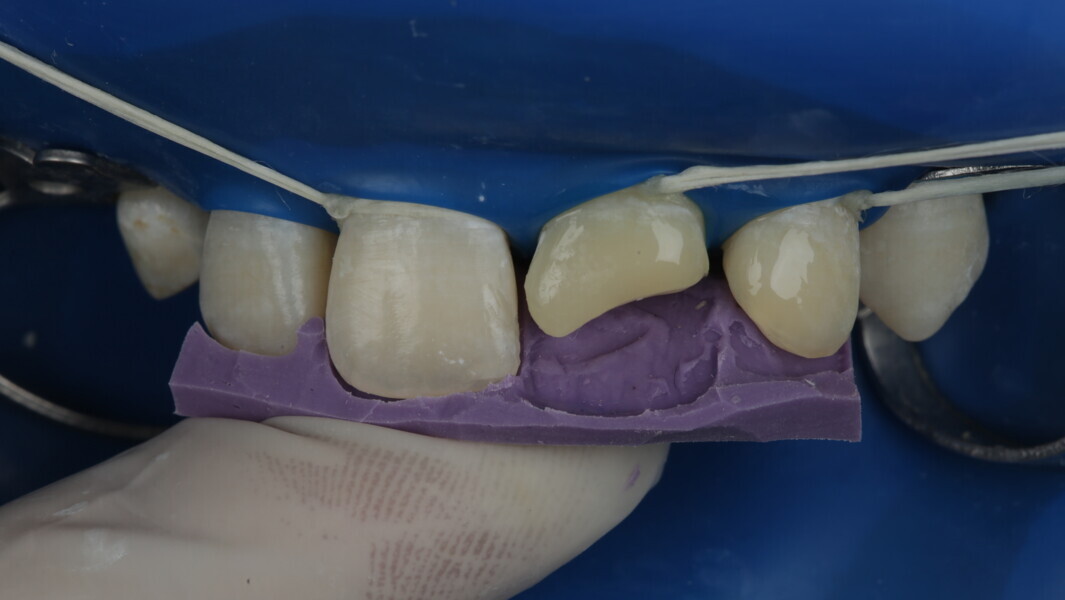

A 10-year-old male patient reported with a complaint of trauma to the upper left central and lateral incisors, involving the enamel and dentin. Direct composite was used in multi-layers and the smile was restored. This article explains detailed steps in the polychromatic layering technique with special emphasis on the finishing and polishing protocol. 3M Espe Filtex Z350 Xt was used with a universal bonding agent.

Fig 1-7: Evaluation and mock up

Fig 8-18: Bonding and palatal shell